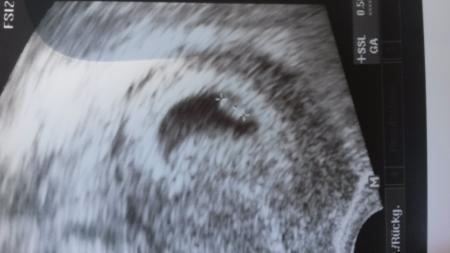

Laut Rechnung wäre ich 9+ 1 und laut Ultraschall 5+5 ...also bissl klein und villt ja doch ehr eins der ersten Feb. Kinder ?!

♡ Hat geblubbert. Wundervoll !!

Im Anhang das wohl kleinste Januar-Baby ;)

Mein Böhnchen ♡♥